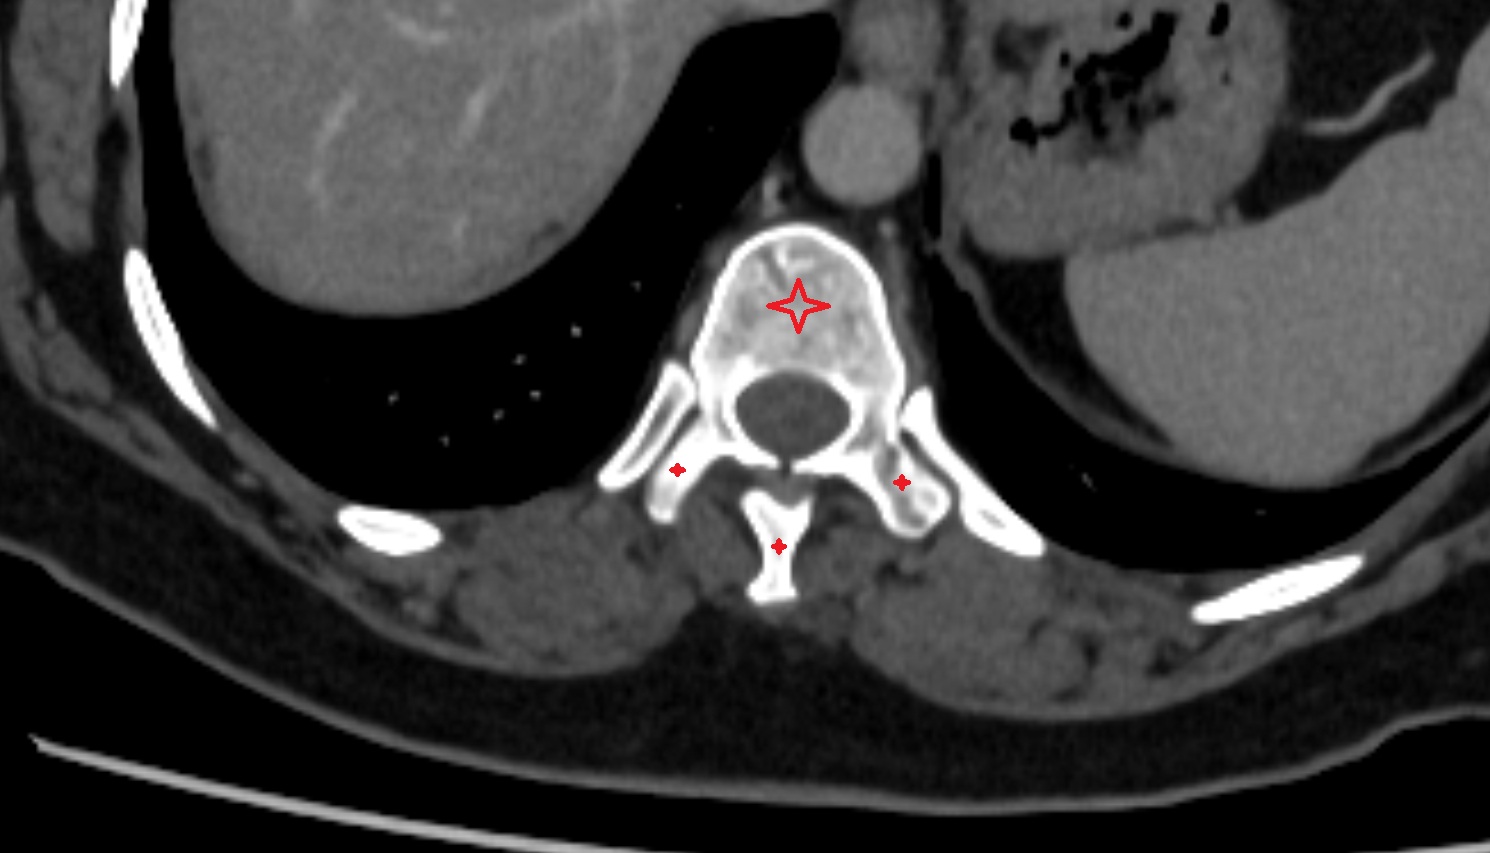

- Spinal dura mater

- Spinal epidural space

- Dorsal traversing nerve root

- Ventral traversing nerve root

- Dorsal exiting nerve root

- Ventral exiting nerve root

- Dorsal root ganglion of spinal nerve